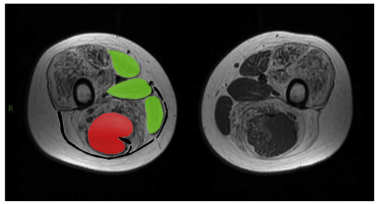

在疾病早期,大腿臀大肌和大收肌即可出现不同程度的脂肪浸润和

图2 “三叶一果”征(图片引自:Zheng Y, Li W, Du J, et al. The trefoil with single fruit sign in muscle magnetic resonance imaging is highly specific for dystrophinopathies[J]. Eur J Radiol, 2015, 84 (10): 1992-1998. )

注:DMD患者肌肉MRI可见缝匠肌、股薄肌、长收肌和半腱肌轻度或无脂肪浸润,其余肌肉受累严重